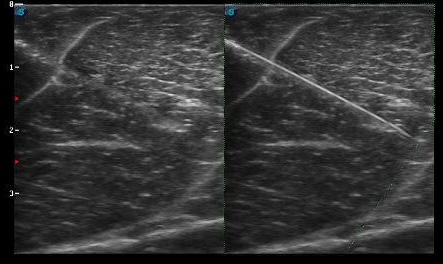

Nel panorama dell’ecografia interventistica, uno dei temi più discussi negli ultimi anni è la visibilità dell’ago durante procedure come biopsie, drenaggi e infiltrazioni.

La novità più rilevante è che la posizione tridimensionale della punta viene sovrapposta direttamente all’immagine ecografica B-mode, offrendo al medico un livello di controllo e sicurezza mai raggiunto con le tecniche tradizionali.

All’interno della nostra gamma di ecografi è infatti disponibile Vis-Needle, un software di ultima generazione progettato proprio per migliorare la visibilità dell’ago in tempo reale. Il sistema riconosce automaticamente l’ago in ingresso, ne enfatizza il profilo e permette di seguirne il percorso con maggiore chiarezza anche in condizioni difficili, contribuendo a un posizionamento più rapido e preciso.